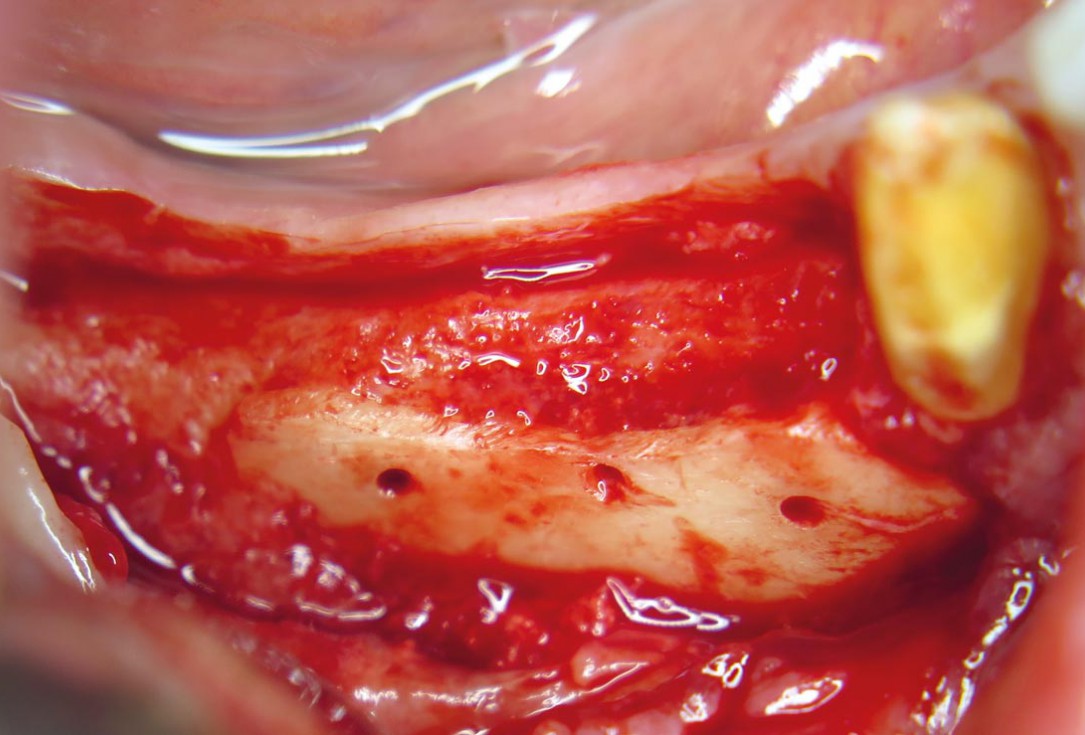

04 / 20 - Decortication of the host bone and fixation of a defect-adapted cortical plateHorizontal ridge augmentation with maxgraft® cortico - M.Sc. E. Kapogianni